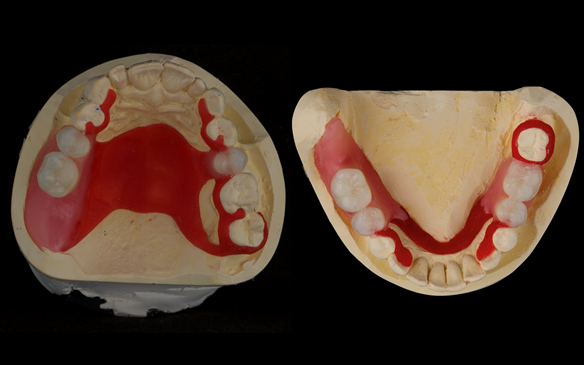

This newsletter describes in step by step detail Angela's transition through immediate partial dentures to crown supported definitive metal based dentures.

The clinical situation and treatment process is shown in detail below with photographs. I (Finlay Sutton) provided the clinical work and Rowan Garstang provided the technical work.